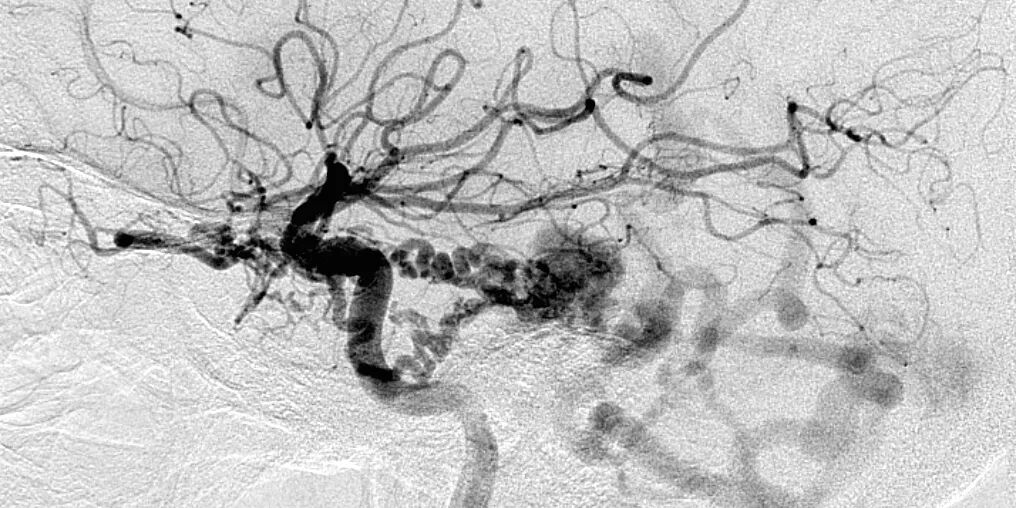

![]()

图3. 侧位颈内动脉血管造影显示天幕/岩部dAVF,由来自颈内动脉的天幕动脉供血,向岩静脉引流,伴后颅窝静脉动脉化。

不论是静脉途径还是动脉途径,都很难经血管内处理岩上窦dAVFs。其供血动脉来自ICA天幕支,如Bernasconi-Casinari动脉,下外侧干和脑膜垂体干。也可来自颈外动脉分支,如脑膜中动脉和咽升动脉。向岩静脉引流,可导致幕上或幕下动脉化的静脉曲张。通常情况下,此类病变经乙状窦后入路夹闭动脉化的岩上窦比较容易。具体会在幕下动静脉瘘章节探讨。

大型的静脉曲张可因压迫三叉神经入脑干区导致三叉神经痛。